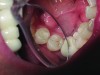

Fig. 4 and Fig. 5 Microorganisms contribute to the localized chemical dissolution of the dental structure.

Yet, most of the patients do not have “ideal” mouths. They present in conditions that are often significantly less than that. They present with disease (Figure 4 and Figure 5). It is the author’s opinion that it is a dentist’s professional responsibility to help move patients from a state of constant disease potential to a state of health. This requires much more than telling patients that they must brush and floss more or better. The physical removal of the bacteria-laden plaque is of course important, but most patients are not fully “trained” on how to really do this well. Perhaps this is because it is assumed that they intrinsically know how. But the reality is that most patients do not fully understand how to remove this biofilm. They often rely on over-the-counter chemical agents and quick fixes that they find on the shelves of their supermarkets and pharmacies that promise to solve their dental issues but are often only superficial remedies.